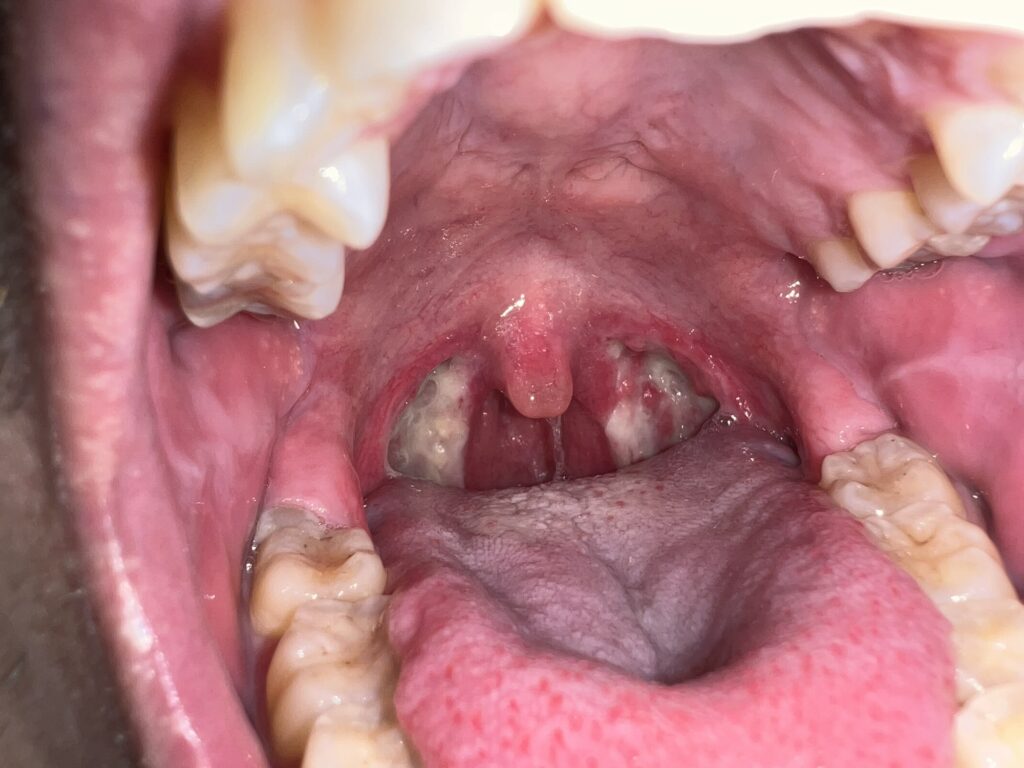

11月17日(手術前)

手術前夜に記念にとパシャリ。中学校2年生の時から共に過ごしてきたポリープちゃんの見納めです。さようなら。